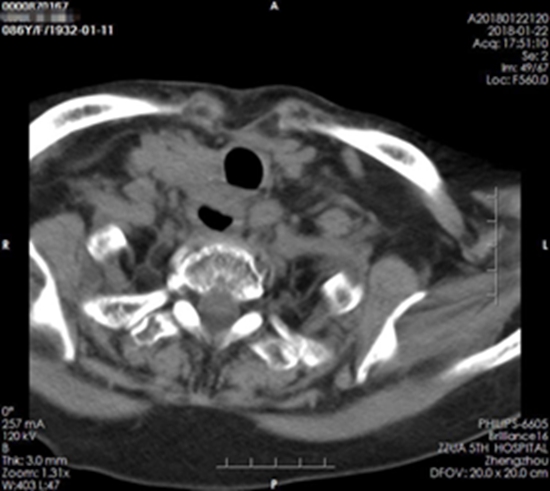

治疗后

短短一个多月,刘奶奶共接受了28次、每次1.8GY,共计50GY的放射治疗,目前所有的症状都已消失,整个人的气色也好了很多。谈到刘奶奶的康复,她的女儿激动地说道:“我妈现在吃饭顺畅了,胸也不闷了,整个人气色好多了,这都归功于王晓瑜主任团队精湛的技术、优质的服务啊!”